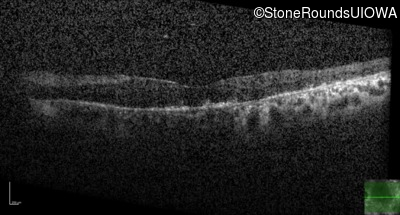

Age at visit: 55 years